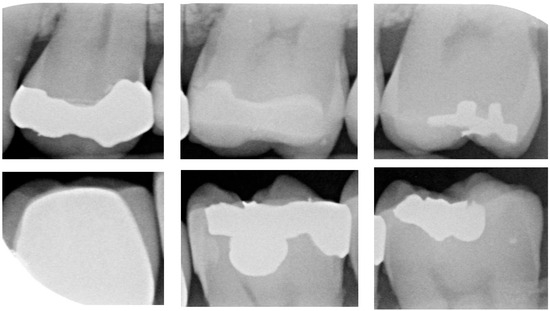

Dental calculus is recognized as a mineralized biofilm that comprises diverse calcium phosphate crystals, which may accumulate on the root surface both supra- and subgingivally [5]. A positive correlation between calculus deposits and periodontitis has been confirmed in multiple studies [6,7]. Despite clear evidence that the surface roughness of calculus alone does not initiate gingivitis, it is important to emphasize that calculus is consistently covered by an unmineralized layer of a viable biofilm [8], which is a primary factor in gingival inflammation [9]. The characteristics of dental calculus are not obvious in a BW image, as shown in Figure 1. The mechanical removal of subgingival plaque and calculus stands as the gold standard in the treatment of periodontitis [10]. While supragingival calculus can easily be seen and removed through sonic/ultrasonic instruments, subgingival calculus is invisible during intra-oral examination. Therefore, the identification of subgingival calculus is critical for the diagnostic process. Radiographic images have been widely used across various applications in the dental field [11]. Subgingival calculus is generally detected during periodontal probing, while radiographic examination can only show calculus on the proximal surfaces [12,13]. Meanwhile, Buchanan et al. [14] reported that the detection of dental calculus on the root surface by radiography had shown low sensitivity but high specificity, and a manual diagnosis can only detect dental calculus in 44% of the 275 datasets that truly have the condition. The detection ability can be increased to 82.2% by staining teeth with 1% methylene blue [15]. Galal et al. [16] observed that periapical films and intra-oral surveys showed comparable efficacy in calculus detection, with a particularly significant enhancement in detection when supplemented with radiographs. In comparison, other dental conditions like caries and periodontal disease have higher detection rates with manual methods. The detection rate for caries is approximately 70–85%, and for periodontal disease, it is around 65–80% [1]. Subgingival calculus documentation is crucial for periodontal assessment. Although clinical assessments are more common for detecting calculus, utilizing BW radiographs offers several advantages in calculus assessment. Firstly, BW images provide a comprehensive view of the tooth structure, allowing for a more thorough examination of interdental spaces where calculus often accumulates. Additionally, BW radiographs enable dentists to visualize areas that may be difficult to access during a clinical examination such as posterior regions. This enhanced visualization can aid in the early detection of calculus, leading to timely interventions and improved patient outcomes.

Figure 1.

Dental calculus symptoms on a BW image: (a) dental calculus symptoms; (b) absence of dental calculus symptoms.